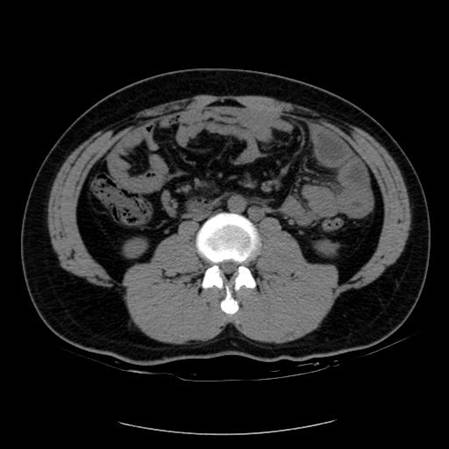

以下是引用zsl6918在2007-6-22 21:08:00的发言:[br]病史较长,反复发作,基本排除恶性病变,腹部定位像可见是小肠梗阻征象,原因无非是肠源性,血管性和神经性的,肠源性的在排除占位后应想到 肠旋转不良的可能,血管性的应想到肠系膜血管的栓塞,神经性的要想到植物神经功能紊乱的可能,本病例应该强化检查帮助诊断,个人感觉旋转不良可能性大。

以下是引用青莲居士在2007-6-24 12:27:00的发言:[br]肠梗阻[br]肝内胆管结石